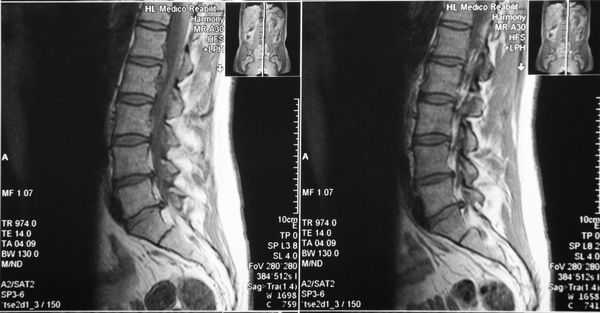

Вестибулярный доступ позволяет решить несколько проблем одновременно во время выполнения функциональной ринопластики. Помимо конхопластики существует возможность выполнения пластики (расширения) грушевидного отверстия при его сужении (костном стенозе) (рис. 5).

Рис. 5. Узкое грушевидное отверстие (костный стеноз).

а — в аксиальной проекции; б — в коронарной проекции (стрелки).

Хирургическая техника, используемая для лечения костного стеноза грушевидного отверстия, впервые описана B. Douglas в 1952 г. [32, 33]. При выполнении пластики грушевидного отверстия необходимо соблюдать осторожность: не расширять отверстие книзу и в заднелатеральном направлении, а только в латеральном направлении, чтобы не повредить лунку зубов и носослезный проток [34, 35]. Лечение обструкции носа, обусловленной дисфункцией носового клапана, направлено на вмешательство, изменяющее внутренний или внешний компонент носового клапана. Внутренний носовой клапан состоит из четырех компонентов, по данным P. Cole: это внутренний угол назального клапана, кость грушевидного отверстия, передняя головка (край) нижней раковины и эректильное тело носовой перегородки. Структурно-анатомическими являются два компонента: угол, образованный между верхним латеральным хрящом и перегородкой, и поперечный диаметр грушевидного отверстия. Два остальных компонента являются мукоцилиарными: головка нижней носовой раковины, а также слизистая оболочка каудальной части перегородки носа (представляющая собой эректильную ткань), расположенная дорсально к нижней носовой раковине. Сужение грушевидного отверстия и скопление эректильной ткани латеральной стенки, особенно нижней носовой раковины, связанные с септальными отклонениями, определяют сопротивление носовому потоку [36].